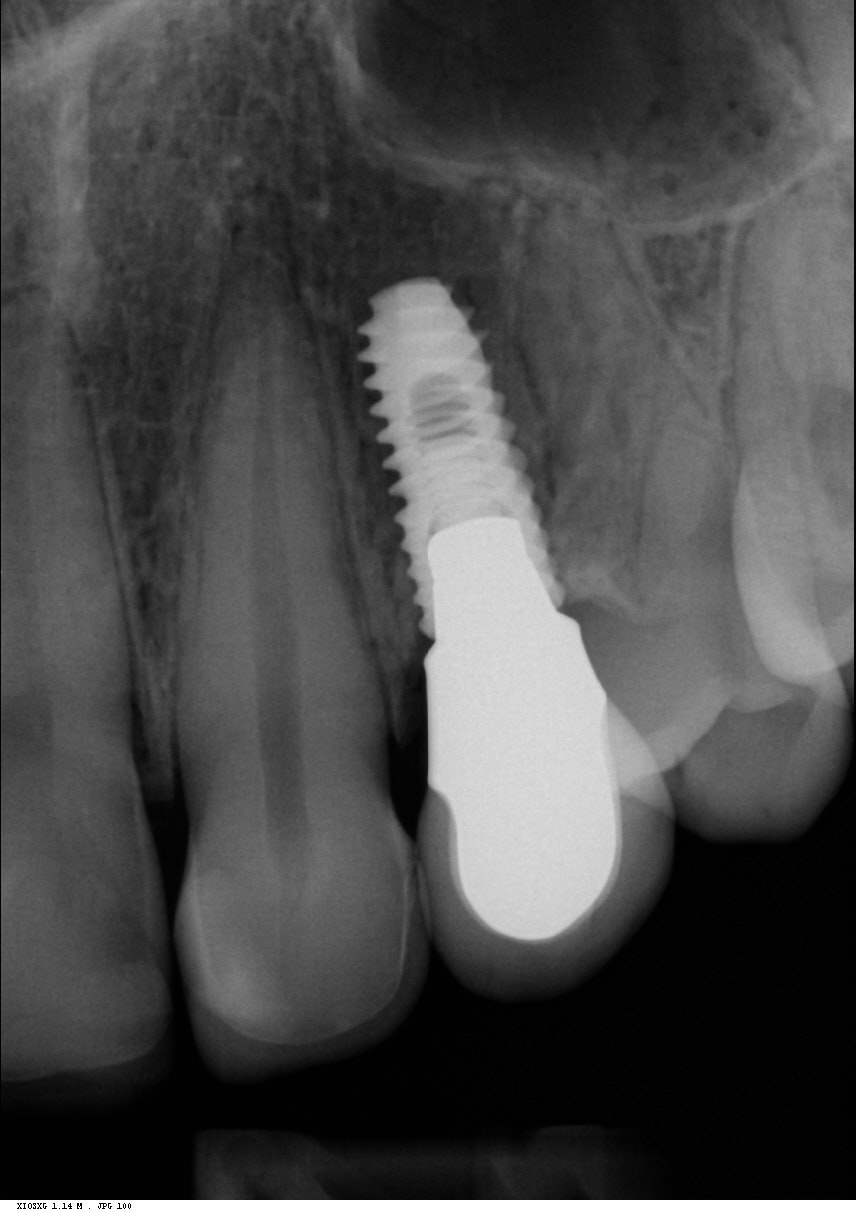

Implantit paikoillaan 1/3

Implantit paikoillaan 2/3

Implantit paikoillaan 3/3